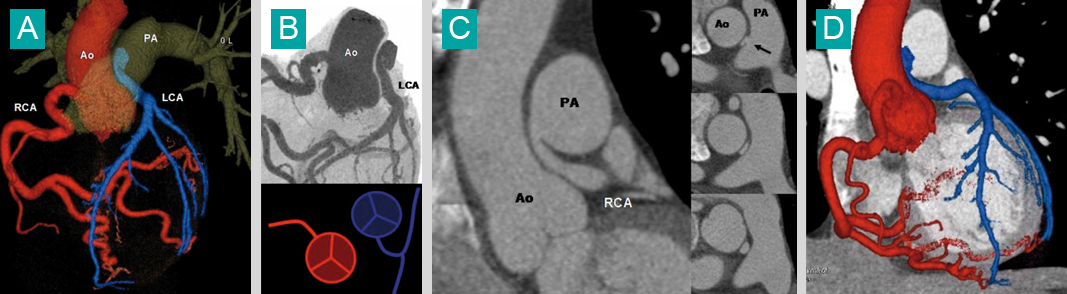

A. Volume rendering (VR) : l'artère coronaire gauche (LCA) en bleu naît de l'artère pulmonaire (PA), artère coronaire droite normale (rouge). Ao : aorte.B. Représentation de l'anomalie de naissance de l'artère coronaire gauche (LCA) en Maximum Intensity projection (MIP).C. Reformatage 2D dans le plan coronal et axial : trajet interartériel (entre l'aorte et l'artère pulmonaire) de l'artère coronaire gauche, qui est comprimée.D. Fusion VR et reformatage 2D des artères coronaires et des cavités cardiaques.